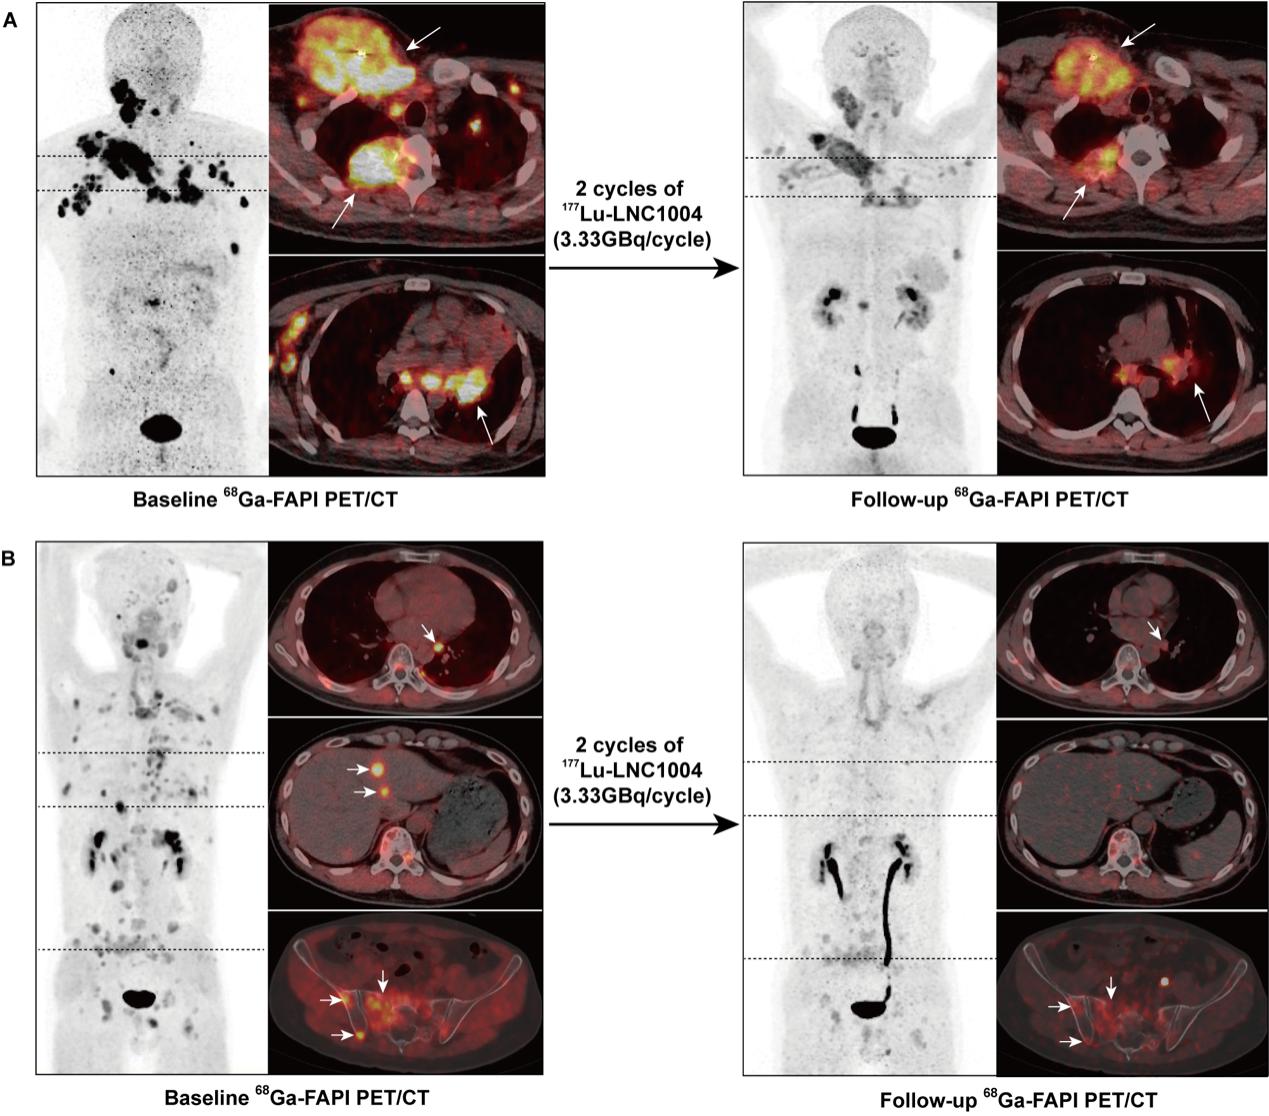

所有的患者在第二輪RLT治療后的第6周根據(jù)RECIST 1.1標(biāo)準(zhǔn)進行了初步療效評價。3例患者(患者4、5、6)達到部分緩解(PR),7例患者疾病穩(wěn)定(SD),客觀反映率(ORR)及疾病控制率(DCR)分別為25%及83%(圖5)。其中患者4的右鎖骨病灶、肋骨病灶及淋巴結(jié)病灶在兩次治療后顯著縮小,值得一提的是因左肺門淋巴結(jié)轉(zhuǎn)移灶導(dǎo)致的阻塞性肺炎也得到了緩解(圖6A)。在患者5中,靶病灶肝轉(zhuǎn)移及非靶病灶的胸腔積液得到了緩解,同時骨、肺轉(zhuǎn)移的靶病灶的最大徑之和在兩次次治療后也顯著縮?。?/span>圖6B)。然而,患者1和8在兩次RLT治療后疾病仍出現(xiàn)進展。其中患者8的靶病灶最大徑之和較前增大,患者1出現(xiàn)新發(fā)皮下轉(zhuǎn)移灶。另外,177Lu-EB-FAPI治療前后靶病灶在68Ga-FAPI-46 PET/CT的SUVmax變化率提示PR的患者顯著降低,而PD的患者顯著增高(圖7)。

圖6. (A) 一例36歲mRAIR-DTC男性接受TKIs治療后疾病進展,接受177Lu-LNC1004 (3.3 GBq/周期)治療?;€68Ga-FAPI-46 PET/CT顯示,68Ga-FAPI-46在包括淋巴結(jié)、椎體和鎖骨在內(nèi)的大多數(shù)轉(zhuǎn)移灶中(左,箭頭)異常濃聚。同時可見左肺門轉(zhuǎn)移淋巴結(jié)轉(zhuǎn)移所致的阻塞性肺炎。2周期治療后,68Ga-FAPI-46 PET/CT顯示腫瘤大小縮小、放射性攝取顯著降低,同時阻塞性肺炎顯著緩解(右,箭頭)。(B)一例42歲mRAIR-DTC男性TKI治療后疾病進展,接受

177Lu-EB-FAPI治療(3.3 GBq/周期)。基線時68Ga-FAPI-46在骨轉(zhuǎn)移、左肺門淋巴結(jié)和肝轉(zhuǎn)移(左,箭頭)中異常濃聚。經(jīng)過2個周期的177Lu-LNC1004治療后, 68Ga-FAPI-46 PET/CT顯示轉(zhuǎn)移灶的大小及范圍顯著縮?。ǜ闻K病灶基本消失),放射性示蹤劑攝取顯著降低(右,箭頭)